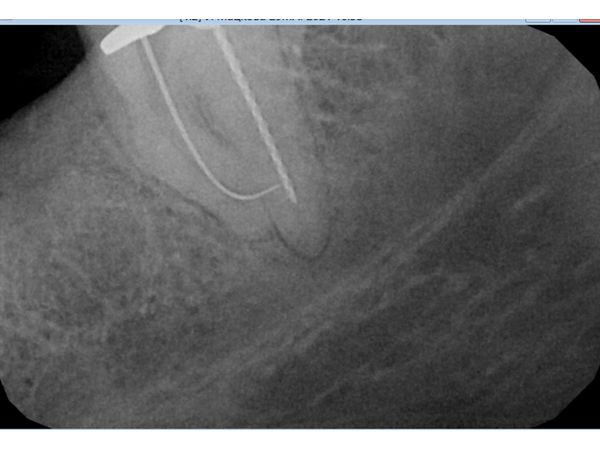

Второй приём прошёл 9 апреля. Женщина ни на что не жаловалась. Ей ввели анестезию, каналы очистили от гидроксида кальция и запломбировали системой BeeFill. После этого в дистальном канале зафиксировали стекловолоконный штифт и восстановили коронку композитным материалом без металла.

После проведённого лечения боль исчезла. Рентгенограмма показала, что женщина может рассчитывать на успешное протезирование.